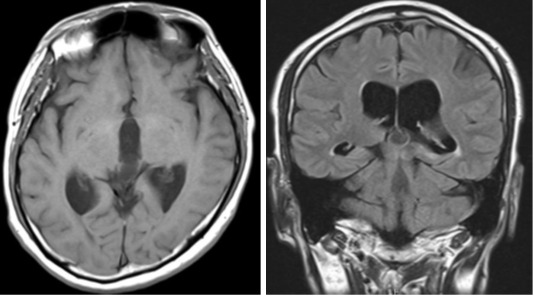

Figure 2 On magnetic resonance imaging, the cyst's signal inside the cyst was stronger than that of the CSF fluid and less strong than the surrounding brain parenchyma and higher than that of the cerebrospinal fluid.

Figure 5 Postoperative magnetic resonance imaging showed the perforated area of the cyst (arrow), and third ventricle (arrowhead).